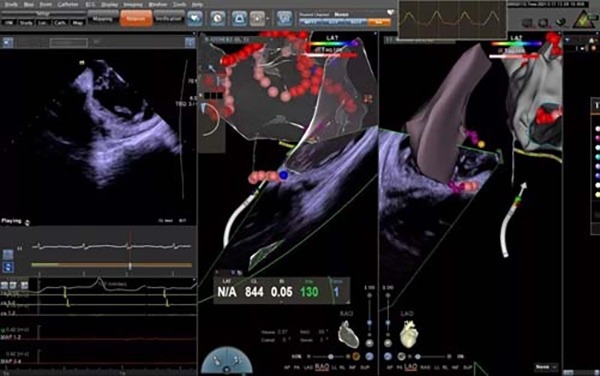

수술은 경전적인2C3L수술식을 적용하였으며 혈관내 초음파 안내관 (ICE)의 지도하에서 무주파수로 심방간격을 관통한후, 좌심방 3D 모형을 신속하고 정확히 수립하고 높은 능율로 폐정맥 전정 격리+심방 지붕선, 승모판 협부선, 삼첨판 협부선 절제를 완성하여 심방세동을 성공적으로 종지하고 동리듬을 회복시켰다. 또한 높은 효율로 제거함으로서 수술 시간을 대폭 단축시키고 환자의 수수중 고통을 감소시켰으며 환자가 수술중 협조를 개선하였다. 공간내 초음파는 X선 노출량을 뚜렷하게 하락시켜 조영제의 사용을 피하였다. 수술중에서 동시에 심낭측정을 실시하여 심낭압전 등 엄중한 합병증을 신속히 발견하여 최대한도로 수술의 안전성과 유효성을 보증하였다.

제거중

초음파 실시간 검사

2. 수술 중에서 ICE지도로 제거한다. 전통X선과 3D 검사 시스템속의 심방세동 제거술과 비교할 경우, ICE는 다차원, 입체적으로 심장 공간내의 구조를 투시하며 제거 안내관의 위치를 더욱 정밀하게 포지셔닝할 수 있다. 안내관이 인접한 상황을 실시간으로 표시하기에 수술의 성공율을 뚜렷하게 향상시킨다. 수술중 심장내의 변화를 실시간으로 검사할 수 있으며 심낭삼출 등 합병증을 가장 빨리 발견할 수 있으며 수술의 안전성을 향상 시킨다. X선의 사용량을 유효하게 감소 시켜 방사가 환자와 의사에 대한 상해를 경감시킨다. ICE안내 심방 간격 첨자로 심방 간격의 가장 좋은 관통 위치를 직관적으로 표시할 수 있으며 안전하고 유효한 첨자를 실행한다. 폐정맥 개구를 정밀하게 포지셔닝할수 있으며 정확한 제거를 위하여 믿음직하고 유효한 방안을 제공한다. 본 기술을 노인 심방세동 환자의 제거치료에 사용하면 제거의 유효성과 안전성을 대폭 향상시킬수 있다.